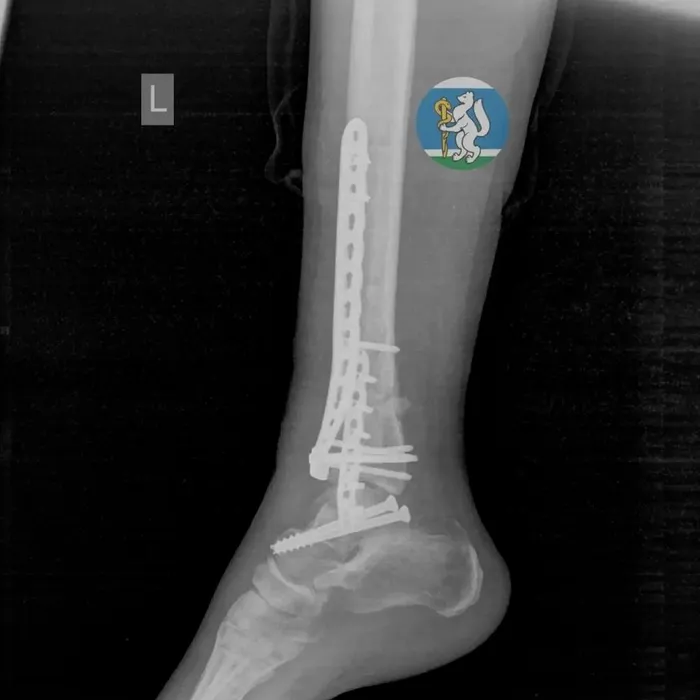

Пострадавшая, как стало известно, выпала из окна, поскользнувшись на подоконнике, когда мыла окна. Каким-то чудом женщина пережила падение, но получила серьезные травмы. Ее увезли в больницу с черепно-мозговой травмой, повреждением позвоночника, переломами таза и ноги.

Медикам удалось реанимировать пострадавшую, а затем они успешно провели несколько операций, «починив» переломанные ноги и таз. В течение месяца екатеринбурженка лежала в больнице, восстанавливаясь, а затем ее выписали домой. Теперь ей предстоит пройти долгую реабилитацию и вернуться к полноценной жизни.